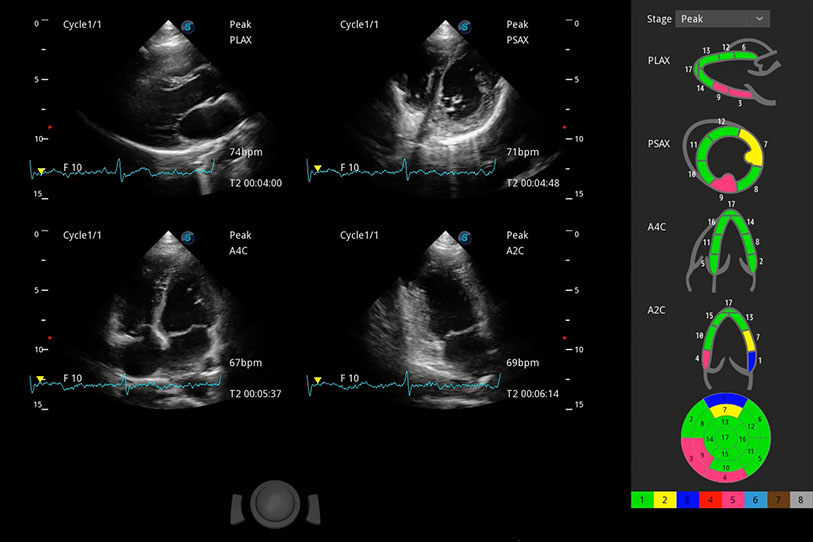

具備多種協(xié)議可選,同時(shí)支持17階段劃分法和專業(yè)的SE報(bào)告。

能夠基于左心室壁追蹤和辛普森法,自動(dòng)計(jì)算射血分?jǐn)?shù),支持多個(gè)可移動(dòng)點(diǎn)描跡,與手動(dòng)測(cè)量相比,極大節(jié)省了動(dòng)物醫(yī)生的時(shí)間和精力。